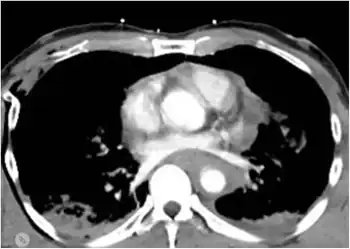

Though not completely reliable, chest X-rays are the first-line investigation,[4] initially used to diagnose this condition when the patient is unstable and cannot be sent to the CT bay. The preferred method of diagnosis used to be CT angiogram until it was found to cause complications in some people; now it is reserved for when CT scans are inconclusive.[4]

The classical findings on a chest X-ray will be widened mediastinum,[4] apical cap, and displacement of the trachea, left main bronchus, or nasogastric tube. A normal chest x-ray does not exclude transection, but will diagnose conditions such as pneumothorax or hydrothorax. The aorta may also be torn at the point where it is connected to the heart. The aorta may be completely torn away from the heart, but patients with such injuries rarely survive very long after the injury; thus it is much more common for hospital staff to treat patients with partially torn aortas.[1] When the aorta is partially torn, it may form a "pseudoaneurysm". In patients who do live long enough to be seen in a hospital, a majority have only a partially torn blood vessel, with the outermost adventitial layer still intact.[2] In some of these patients, the adventitia and nearby structures within the chest may serve to prevent severe bleeding.[2] After trauma, the aorta can be assessed by a CT angiogram or a direct angiogram, in which contrast is introduced into the aorta via a catheter.